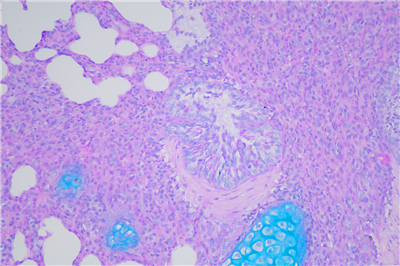

PAS染色步骤:

1脱蜡:65度30分钟,二甲苯脱蜡 5min×2次

2水化:将脱蜡后的切片经100%酒精,95%酒精,85%酒精,75%酒精,双蒸水各3min

3 入阿利新蓝染色液,染色15分钟。

4 蒸馏水洗3次,每次1-2分钟。

5 入过碘酸溶液,氧化5分钟

6入Schiff Reagent,浸染15分钟。

7 倾去Schiff Reagent,流水冲洗10分钟。

8(可选)入Leagene苏木素染色液,染核1-2分钟。

9用酸性分化液分化2-5秒,水洗。

10用Scott蓝化液反蓝,水洗3分钟。

11 逐级常规乙醇脱水。二甲苯透明,中性树胶封固。

12通过显微镜拍照,采集分析样本相关部位。